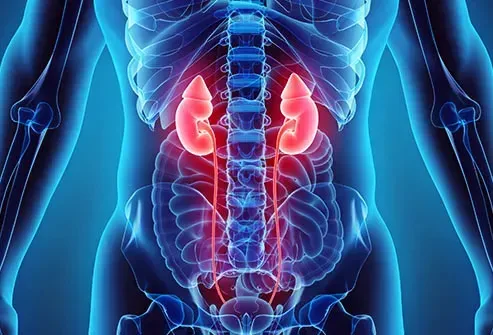

Umístění: Ledviny

Také se nazývá trombóza renální žíly tyto sraženiny obvykle rostou pomalu a většinou u dospělých. Pravděpodobně nebudete mít příznaky, pokud se kus nerozbije a uloží se do plic. Zřídka se u dětí může stát rychle a způsobit nevolnost a zvracení. Můžete mít také krev ve vašem čůrání a jít méně často.